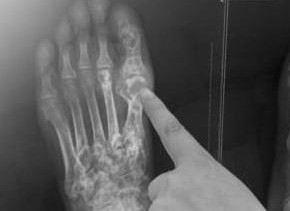

痛風是一種因高尿酸血癥導致的關節(jié)炎癥,常表現(xiàn)為關節(jié)紅腫熱痛,嚴重影響患者的生活質量,隨著現(xiàn)代生活方式的改變,痛風患者日益增多,尋找有效的治療方法顯得尤為重要,本文旨在探討治療痛風的最佳方法,幫助患者早日擺脫病痛。

在治療痛風的過程中,患者需了解痛風成因、癥狀及現(xiàn)有治療方法,以便選擇最適合自己的治療方案,本文關鍵詞“治療痛風的最佳方法”涉及痛風的有效治療途徑,包括藥物治療、生活調整及自然療法等。